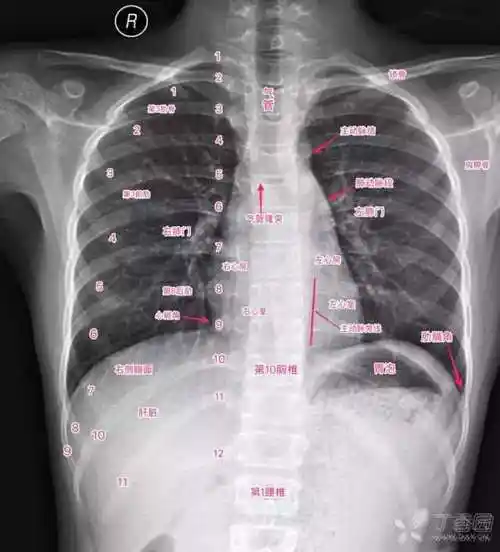

气胸x线胸片图解

x线读片技巧ppt